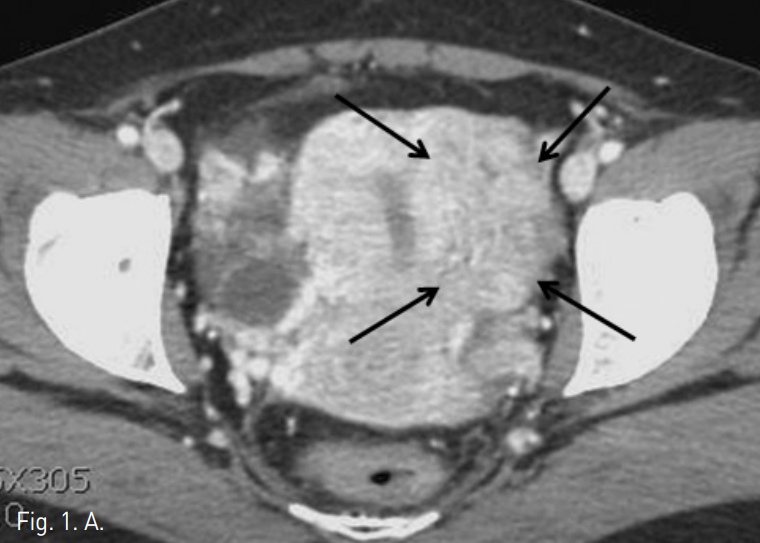

Fig. 1

A, B. Axial CT scan shows 8 x 6 cm sized, convoluted worm-like mass (arrows in A) on the left side of the uterine wall along the uterine vein (arrow in B).